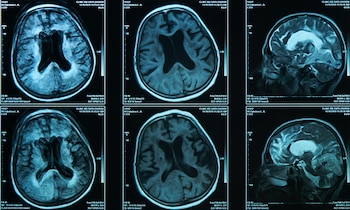

“Estamos realmente en una situación estadística muy improbable”, aclara Jean-Charles Lambert, director de investigación del Inserm y especialista en la enfermedad de Alzheimer. Los científicos han registrado durante una década todo tipo de imágenes del cerebro de este hombre, análisis, seguimiento biológico... “Un expediente extremadamente completo”, según el profesor Philippe Amouyel. A pesar de todo lo estudiado, no se ha podido concretar cuál es la razón tras esta insólita situación.

El caso presentado en la Nature Medicine sin duda inaugurará un nuevo enfoque terapéutico para el Alzheimer, consideran los autores. Además, resulta especialmente interesante si tenemos en cuenta que las imágenes del cerebro del hombre muestran que ya se ha producido esa primera etapa del proceso que conduce al desarrollo de la enfermedad.

“En primer lugar, se producen lesiones de un tipo de proteína pegajosa (amiloide) que se extiende por el cerebro entre las neuronas. En segundo lugar, se desarrollan anomalías en el interior de las neuronas, la ‘hiperfosforilación de la proteína Tau’, que conduce a la muerte de las neuronas”, resume el profesor Philippe Amouyel, director general de la Fundación Alzheimer de Francia.

No obstante, los científicos observaron en el cerebro de este hombre numerosos depósitos de amiloide, incluso más que en ciertas personas sintomáticas de su familia. La segunda etapa no ha llegado a producirse.